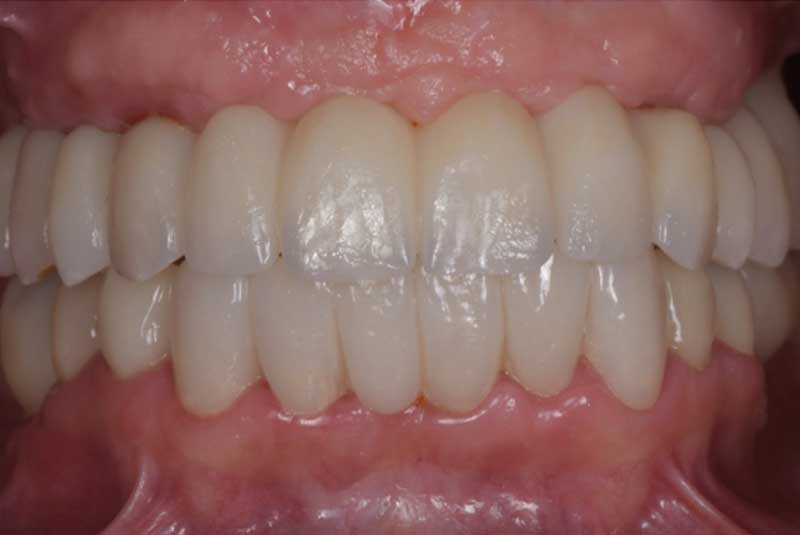

All on 6: Facial cut back (PFZ) Zirconia Full arch prosthesis for Maxilla and Mandible Before & After